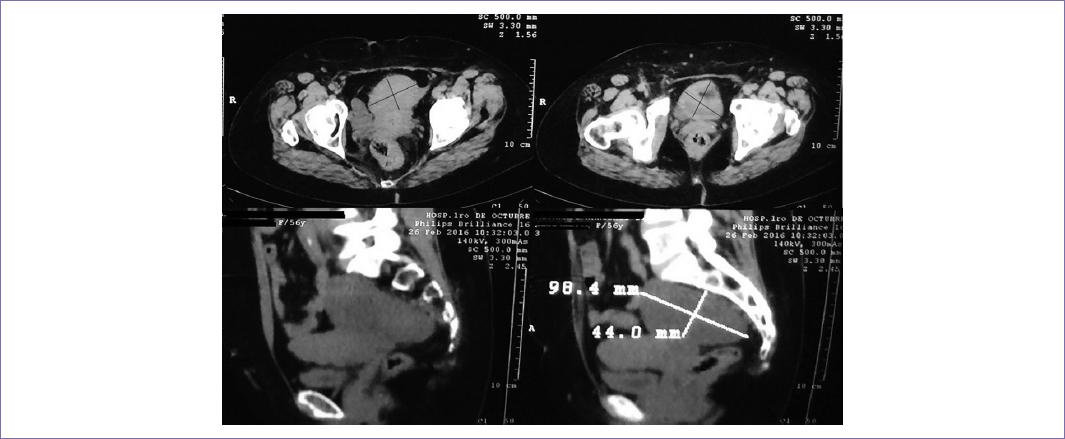

El US transvaginal reveló miomatosis uterina de medianos elementos de tipo intramural con degeneración cálcica; así como masa sólida retroperitoneal de forma piriforme con dimensiones de 95 x 37 mm; a la aplicación de US Doppler no hubo presencia de vascularidad. Conjuntamente le fue realizada una tomografía computarizada (TC) (Fig. 1) más venografía (Fig. 2), la cual mostró trombosis parcial de la vena cava inferior, desde la bifurcación de las venas ilíacas, hasta aferencia de venas suprahepáticas; por tal motivo, hubo necesidad de colocar un filtro en vena cava por encima de la aferencia de las venas renales.

Figura 1 TC abdominal que reveló una masa heterogénea de tejido blando con dimensiones de 98.4 x 44 mm (corte sagital), de densidad baja y con bordes bien delimitados. La extirpación quirúrgica y el análisis histopatológico ayudaron a confirmar el diagnóstico de schwannoma.